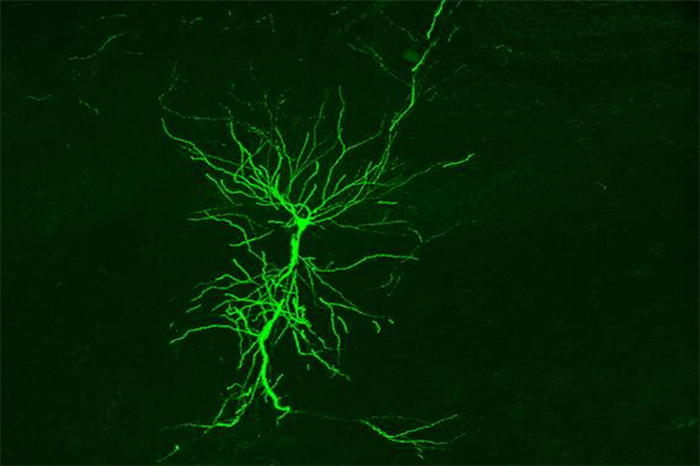

Madrid, España. Un equipo internacional de investigadores ha conseguido canalizar la luz a través de nanoestructuras para estudiar las regiones más profundas del cerebro.

La nueva tecnología consiste en una fibra óptica, con un diámetro menor al de un cabello humano, en cuyo interior alberga las denominadas estructuras plasmónicas, unas nanoestructuras metálicas que pueden ajustarse para responder a un estímulo de luz que viaja por la fibra.

El dispositivo dirige la luz de forma precisa y genera una interacción física con las células para observar sus propiedades.

“Se trata de una fibra óptica modificada para enviar y recibir luz. La sonda permite iluminar las moléculas del tejido cerebral y amplificar la luz que estas reflejan, generando patrones espectrales en función de las propiedades de cada tipo de molécula”, ha explicado la investigadora del Instituto Cajal del CSIC Liset Menéndez de la Prida, directora de la aplicación neurocientífica del proyecto y experta en el estudio de la epilepsia.